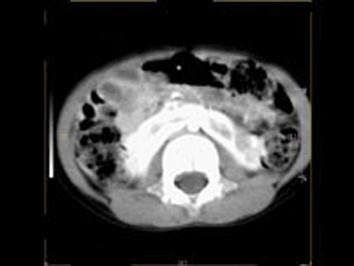

女,6个月,CT扫描如图所示,下列说法错误的是 ( )A、异位肾B、马蹄肾C、双侧肾门朝向前内方D、双肾下极融合E、双侧肾盂积水

问题 女,6个月,CT扫描如图所示,下列说法错误的是 ( )

选项 A、异位肾 B、马蹄肾 C、双侧肾门朝向前内方 D、双肾下极融合 E、双侧肾盂积水

答案 A